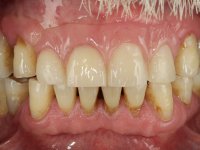

Segunda Fase

6 meses após a colocação da ponte, o paciente sofre um novo traumatismo comprometendo a viabilidade dos dentes 1.2 e 1.1. Foi realizada uma prótese removível acrílica para reabilitar provisoriamente o paciente enquanto foram extraídos os dentes 1.2 e 1.1 e foi colocado o implante no local do dente 1.1. Passados 3 meses foi realizada uma impressão ao implante colocado no 1.1 e simultaneamente foi feito um arrasto da ponte dos dentes 2.1 e 2.2. Para esse efeito no implante 2.1 foi utilizado um parafuso de uma peça de transferência. Dessa forma conseguiu-se impressionar corretamente a arquitetura gengival do sector antero-superior. O objetivo era simultaneamente impressionar corretamente esta zona e aproveitar a estrutura metálica desta ponte para confecionar a nova ponte de 4 elementos. Foi colocado um parafuso de cicatrização no implante 2.1 e foram acrescentados os dentes 2.1 e 2.2 na prótese removível. Com perícia laboratorial foi criada uma nova infraestrutura metálica de 4 elementos assente nos implantes 1.1 e 2.1 e com os elementos pônticos suspensos 1.2 e 2.2. No implante 2.1 manteve-se a conexão interna ao implante no implante 1.1 optou-se por uma peça intermédia facilitando a inserção da infraestrutura. A nova infraestrutura foi verificada em boca. Como pode ter havido alguma alteração da arquitetura gengival com a remoção da ponte e colocação do parafuso de cicatrização no 2.1, foi feita uma chave de silicone para permitir uma impressão de arrasto da infraestrutura metálica. Uma nova gengiva artificial foi realizada no modelo de trabalho de acordo com esta impressão de arrasto. Foi colocada cerâmica de tonalidade coronária e gengival. A peça protética foi aparafusada lentamente em boca para permitir uma adaptação dos tecidos moles. Após o correto assentamento e verificação imagiológica a ponte foi definitivamente apertada em boca e os orifícios de acesso obturados. Independentemente dos infortúnios que o paciente teve, pude ter a satisfação de o ver contente com esta reabilitação.